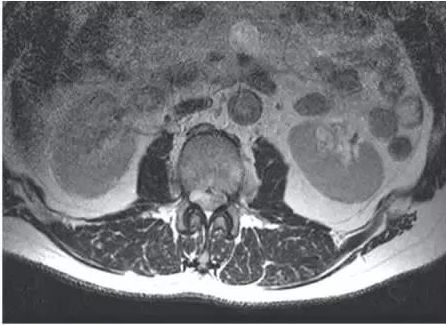

CT、MRI检查的后的图片一般会有水平面、冠状面、矢状面。简单的说,水平面也叫横断面,它与地面平行,是将人体分为上、下两部分的切面。下图是腰椎的一个MRI的横断面图。